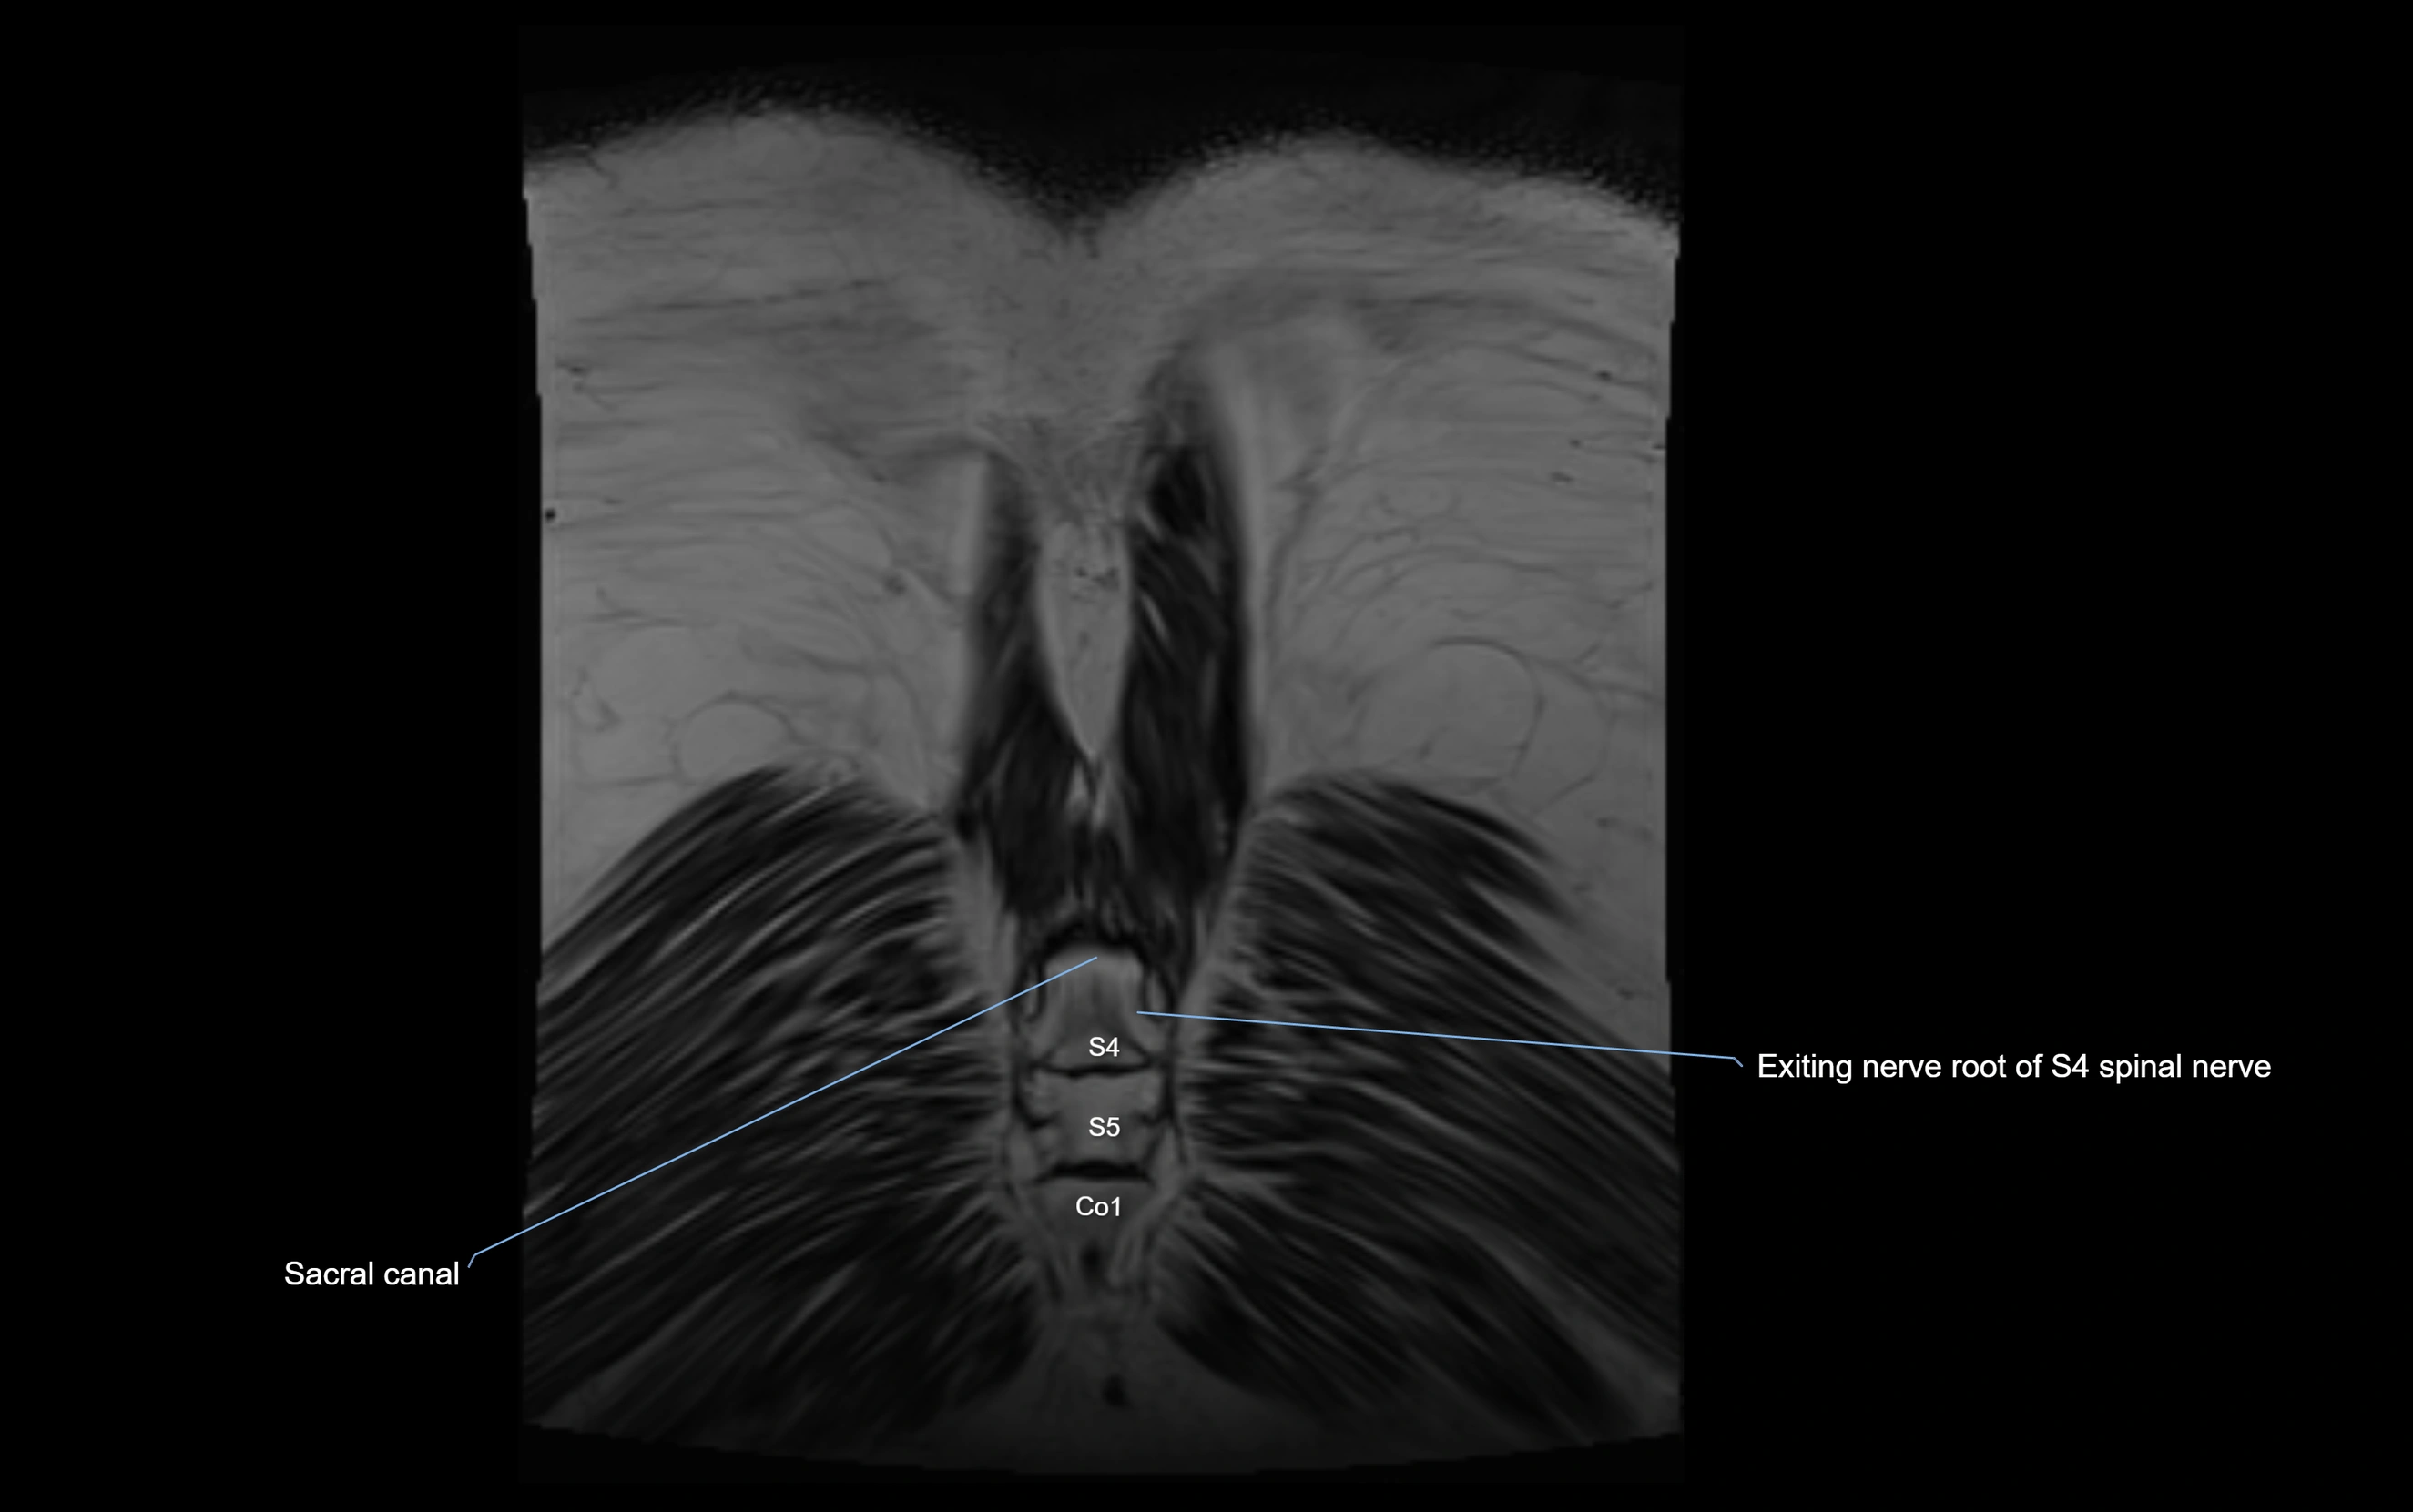

MRI image

image